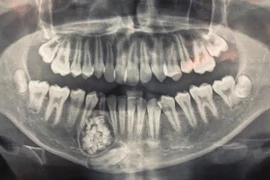

Trong quá trình phẫu thuật, các bác sĩ Bệnh viện Hữu nghị Việt Nam - Cuba Đồng Hới phát hiện và loại bỏ hơn 28 chiếc răng lớn nhỏ trong khối u của bé trai 9 tuổi.

Bệnh viện Đa khoa tỉnh Khánh Hòa cho biết các bác sĩ vừa thực hiện ca phẫu thuật, lấy ra gần 100 cái răng trong khối u hàm dưới của 1 bệnh nhân 13 tuổi.